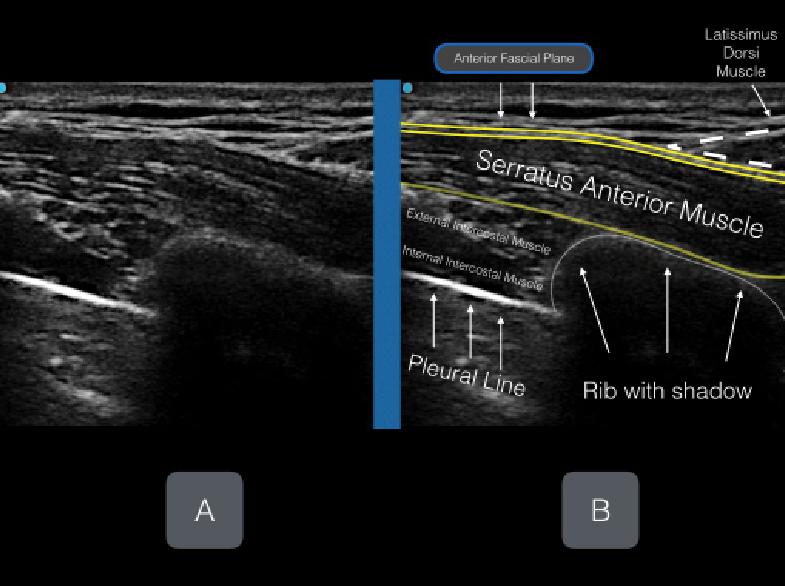

Figures 5A & B: Unlabeled (A) and labeled (B) ultrasound image.